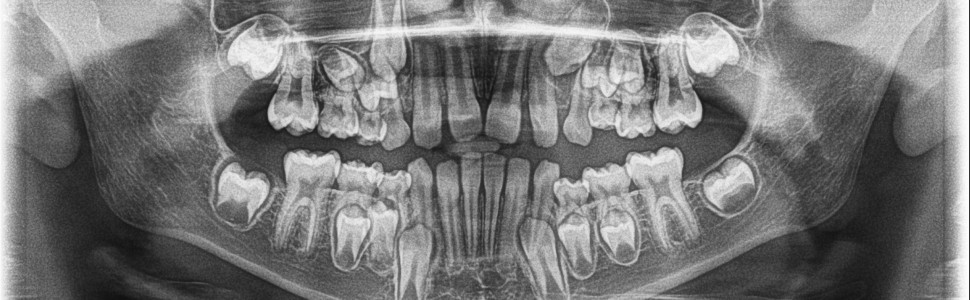

Reinkluzja zębów (reinclusio dentis) jest jedną z form zaburzeń biologicznego wyrzynania się zębów. Zjawisko intruzji zębów dotyczy najczęściej mlecznych zębów trzonowych. W pracy opisano przypadek dziesięcioletniego chłopca, u którego stwierdzono reinkluzję wszystkich pierwszych zębów trzonowych mlecznych.

Reinclusion of teeth (reinclusio dentis) is one of the forms of disorders of biological teeth eruption. The phenomenon of tooth intrusion affects most often primary molars. The paper describes the case of a 10-year-old boy who was found to have reinclusion of all first primary molars.